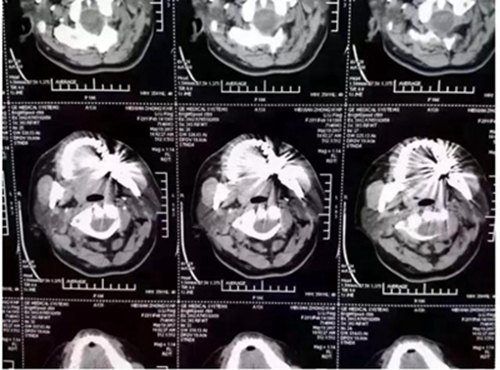

口內(nèi)有金屬烤瓷牙做核磁共振,CT,以烤瓷牙為中心呈現(xiàn)放射狀影像,無法看清周圍組織,影響臨床診斷,建議條件允許的朋友還是選擇二氧化鋯全瓷冠修復(fù),以免帶來不必要的麻煩!

另外,非金屬的二氧化鋯對(duì)X線卻無任何阻擋,只要鑲?cè)攵趸喛敬裳?,日后做頭顱X線、CT、核磁共振檢查時(shí)都不需要拆掉假牙,省去很多麻煩。本文之前曾報(bào)道《牙齒阻礙磁共振?那是你沒有用二氧化鋯牙》

2.因金屬內(nèi)冠的存在,透光性、色澤和形態(tài)與自然牙存在較大的區(qū)別,更會(huì)在燈光下產(chǎn)生青灰色的效果。同時(shí)金屬瓷牙在液體口腔酸堿環(huán)境細(xì)菌作用下不穩(wěn)定,患者在做CT核磁共振時(shí)金屬有一定的干。